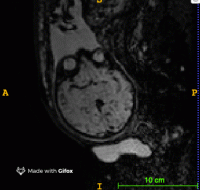

This project aims at developing new preprocessing strategies for in-utero functional MRI with the focus on the following research lines

(1) Development of new high resolution reconstruction and motion correction techniques

Objectives: Investigation and development of a high resolution reconstruction and motion correction technique for resting state functional MRI acquisitons of fetuses.